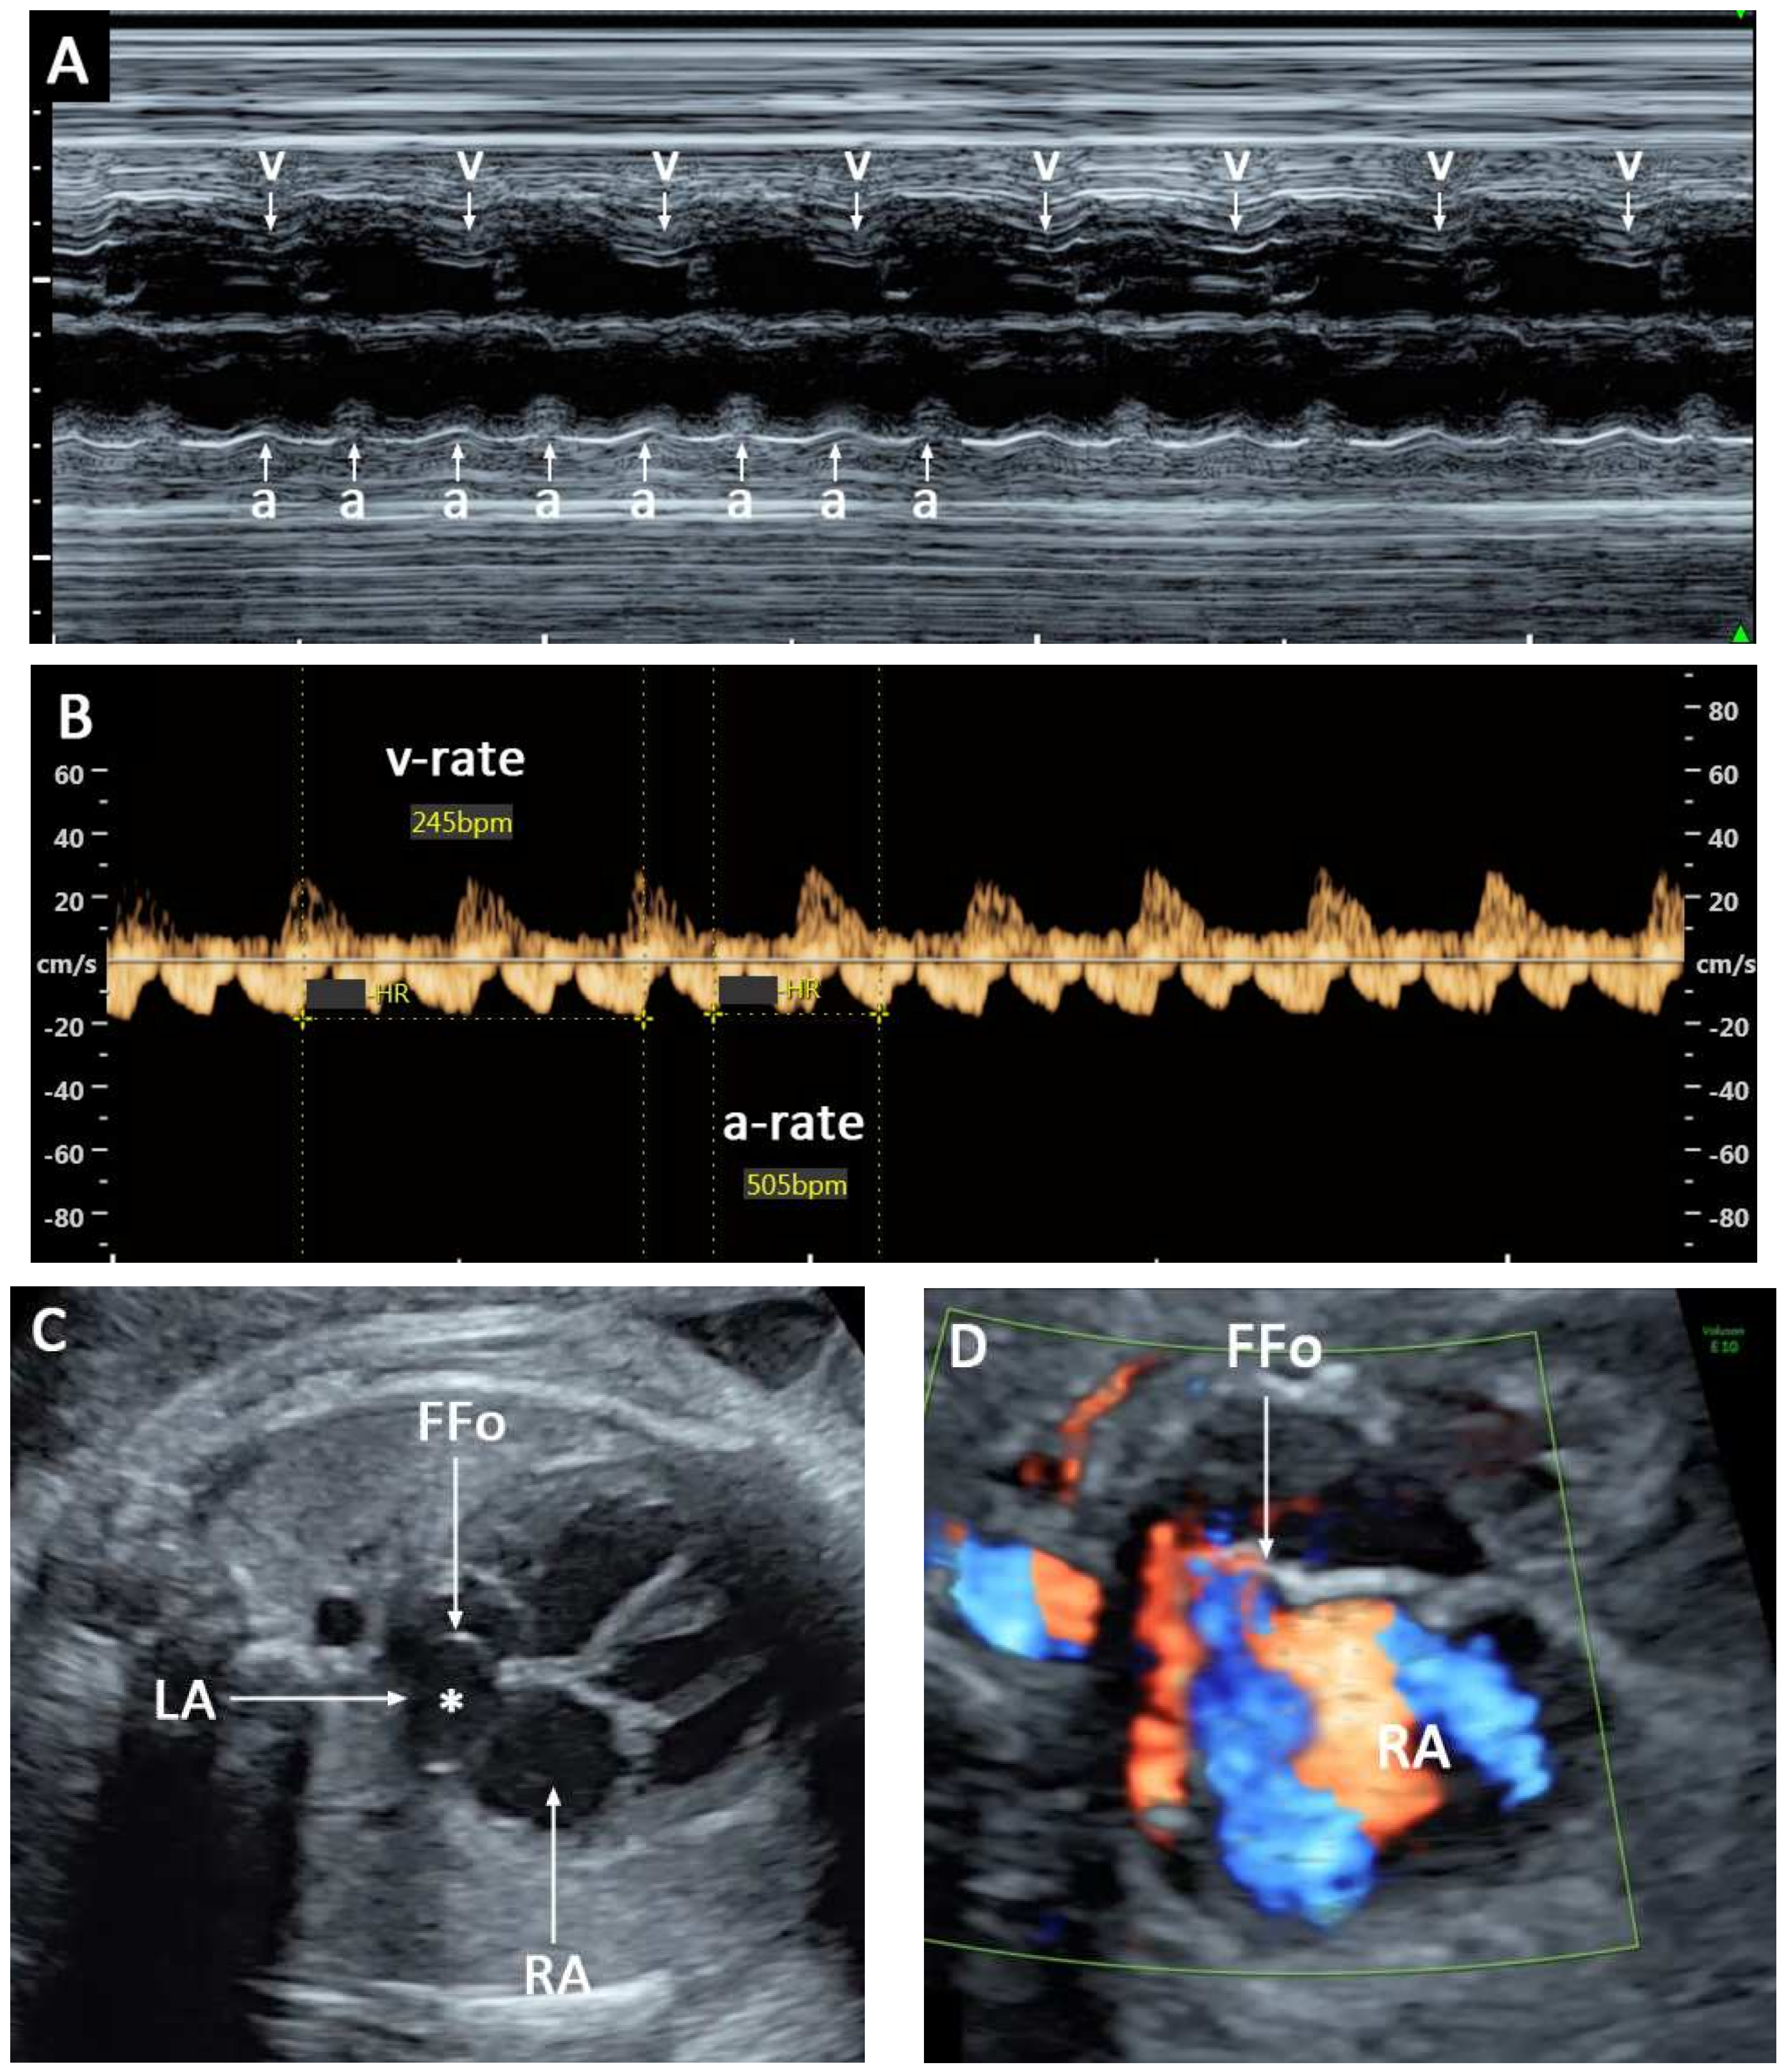

2. Case Series